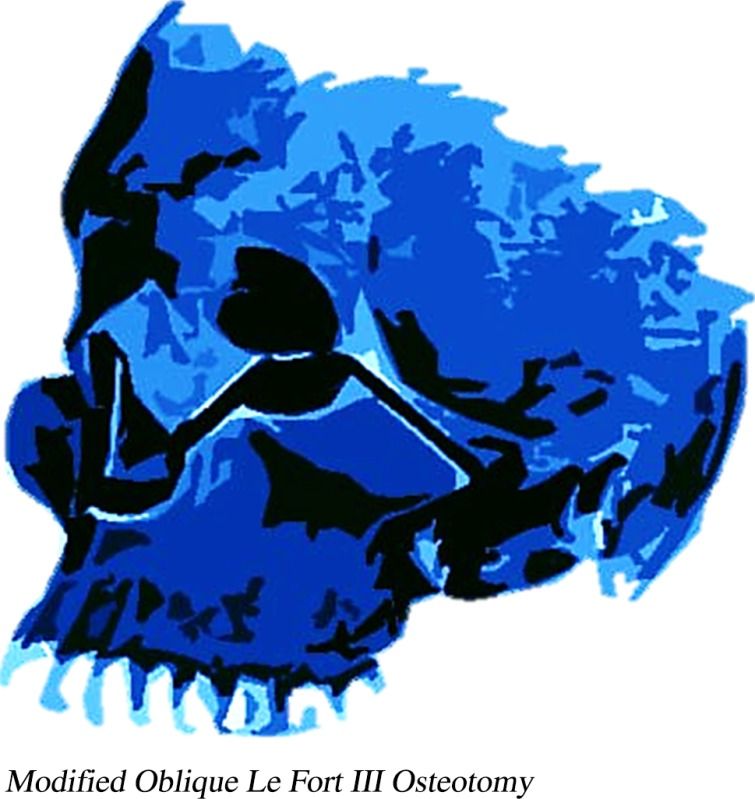

It moves cheekbones upward, give so much under eye support and even change orbital shape. Also widen face and change gonial angle. Is it modified lefort 3?